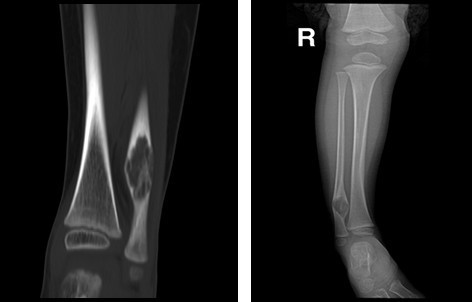

单发型病变部位在髓腔内,长管状骨的干骺端或骨干中心位或偏心位。骨皮质变薄形成缺损,呈模糊的髓腔内放射透明区,常形容为磨砂玻璃状。多发型纤维结构不良常累及数骨,同侧的髂骨、股骨、胫骨、腓骨常被累及。四肢长骨病变常累及骨的全部,髓腔宽窄不均,其增宽处骨皮质变薄并扩张。部分高度膨胀,其中有囊性改变,常表现为病理性骨折。X线表现为溶骨范围界限不清,骨皮质缺损和临近软组织肿块通常提示恶变。